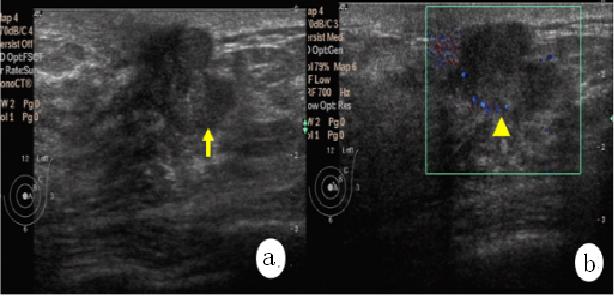

超声发现乳腺浸润癌

然后,医生会利用乳腺彩超、专用钼靶X线或MRI等影像学检查来获取进一步的诊断信息,部分患者还会结合穿刺活检、乳腺导管造影等,以利于制定个性化的治疗方案。